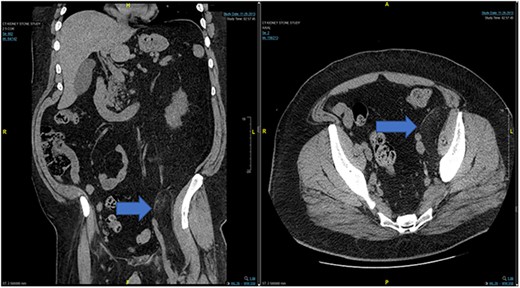

Case 1: CT (axial and coronal view), blue arrow marks hibernoma.

A 58-year-old male patient with a medical history of hypertension, type 2 diabetes mellitus, neuropathy and multiple kidney stones presents to the emergency department with complaints of dysuria, frequency of micturition and urgency for the past 4 days. Patient denied any fever. He also described a sharp shooting pain sensation along his left leg that was intermittent and associated with movement. He elaborated that it felt like it mimicked the chronic neuropathy pain which the patient was used to having, but the pain would begin after ambulating for a short distance, such as across a room. It was incapacitating. He denied any recent trauma.

In the emergency department, vital signs were remarkable for elevated blood pressure of 166/81, but otherwise stable and afebrile. WBC count was elevated at 15.4 with left shift and hemoglobin was low at 9.6. Complete Metabolic Panel was notable for hyponatremia of 128, and mildly elevated BUN/serum creatinine of 26/1.5 which was slightly higher than his baseline of 17/1.3. Liver function tests were unremarkable. UA showed likely UTI with positive esterase, high RBC/WBC and bacteria and protein. A CT of the abdomen and pelvis was done, showing a left non-obstructing kidney stone and a left retroperitoneal fat density with stranding along the left iliopsoas measuring 12.6 × 8.1 cm × 3.7 cm, which was described as possibly a part of infectious or malignant process (Fig. 5). Subsequently, patient’s prior CT scans were available to be reviewed and it showed the same lipomatous mass 9 years earlier. (Fig. 6). Given the patient’s symptoms of left lower extremity pain and the possibility that the mass was responsible, a CT-guided core biopsy was ordered for diagnosis to rule out a malignant process as operative intervention was being contemplated. Pathology report of the core biopsy showed lobules of univacuolated adipocytes divided by thin septa. There were frequent multivacuolated adipocytes with small round nuclei, reminiscent of brown fat cells. No enlarged hyperchromatic cells, mitotic figures nor necrosis are seen. The findings supported the diagnosis of the lipoma variant of hibernoma (Fig. 4). Given the chronicity of the mass, the near identical size over 9 years and the diagnosis made from core biopsy, it was determined that the hibernoma was not the likely source of the patient’s LLE pain and hence the mass was not excised.